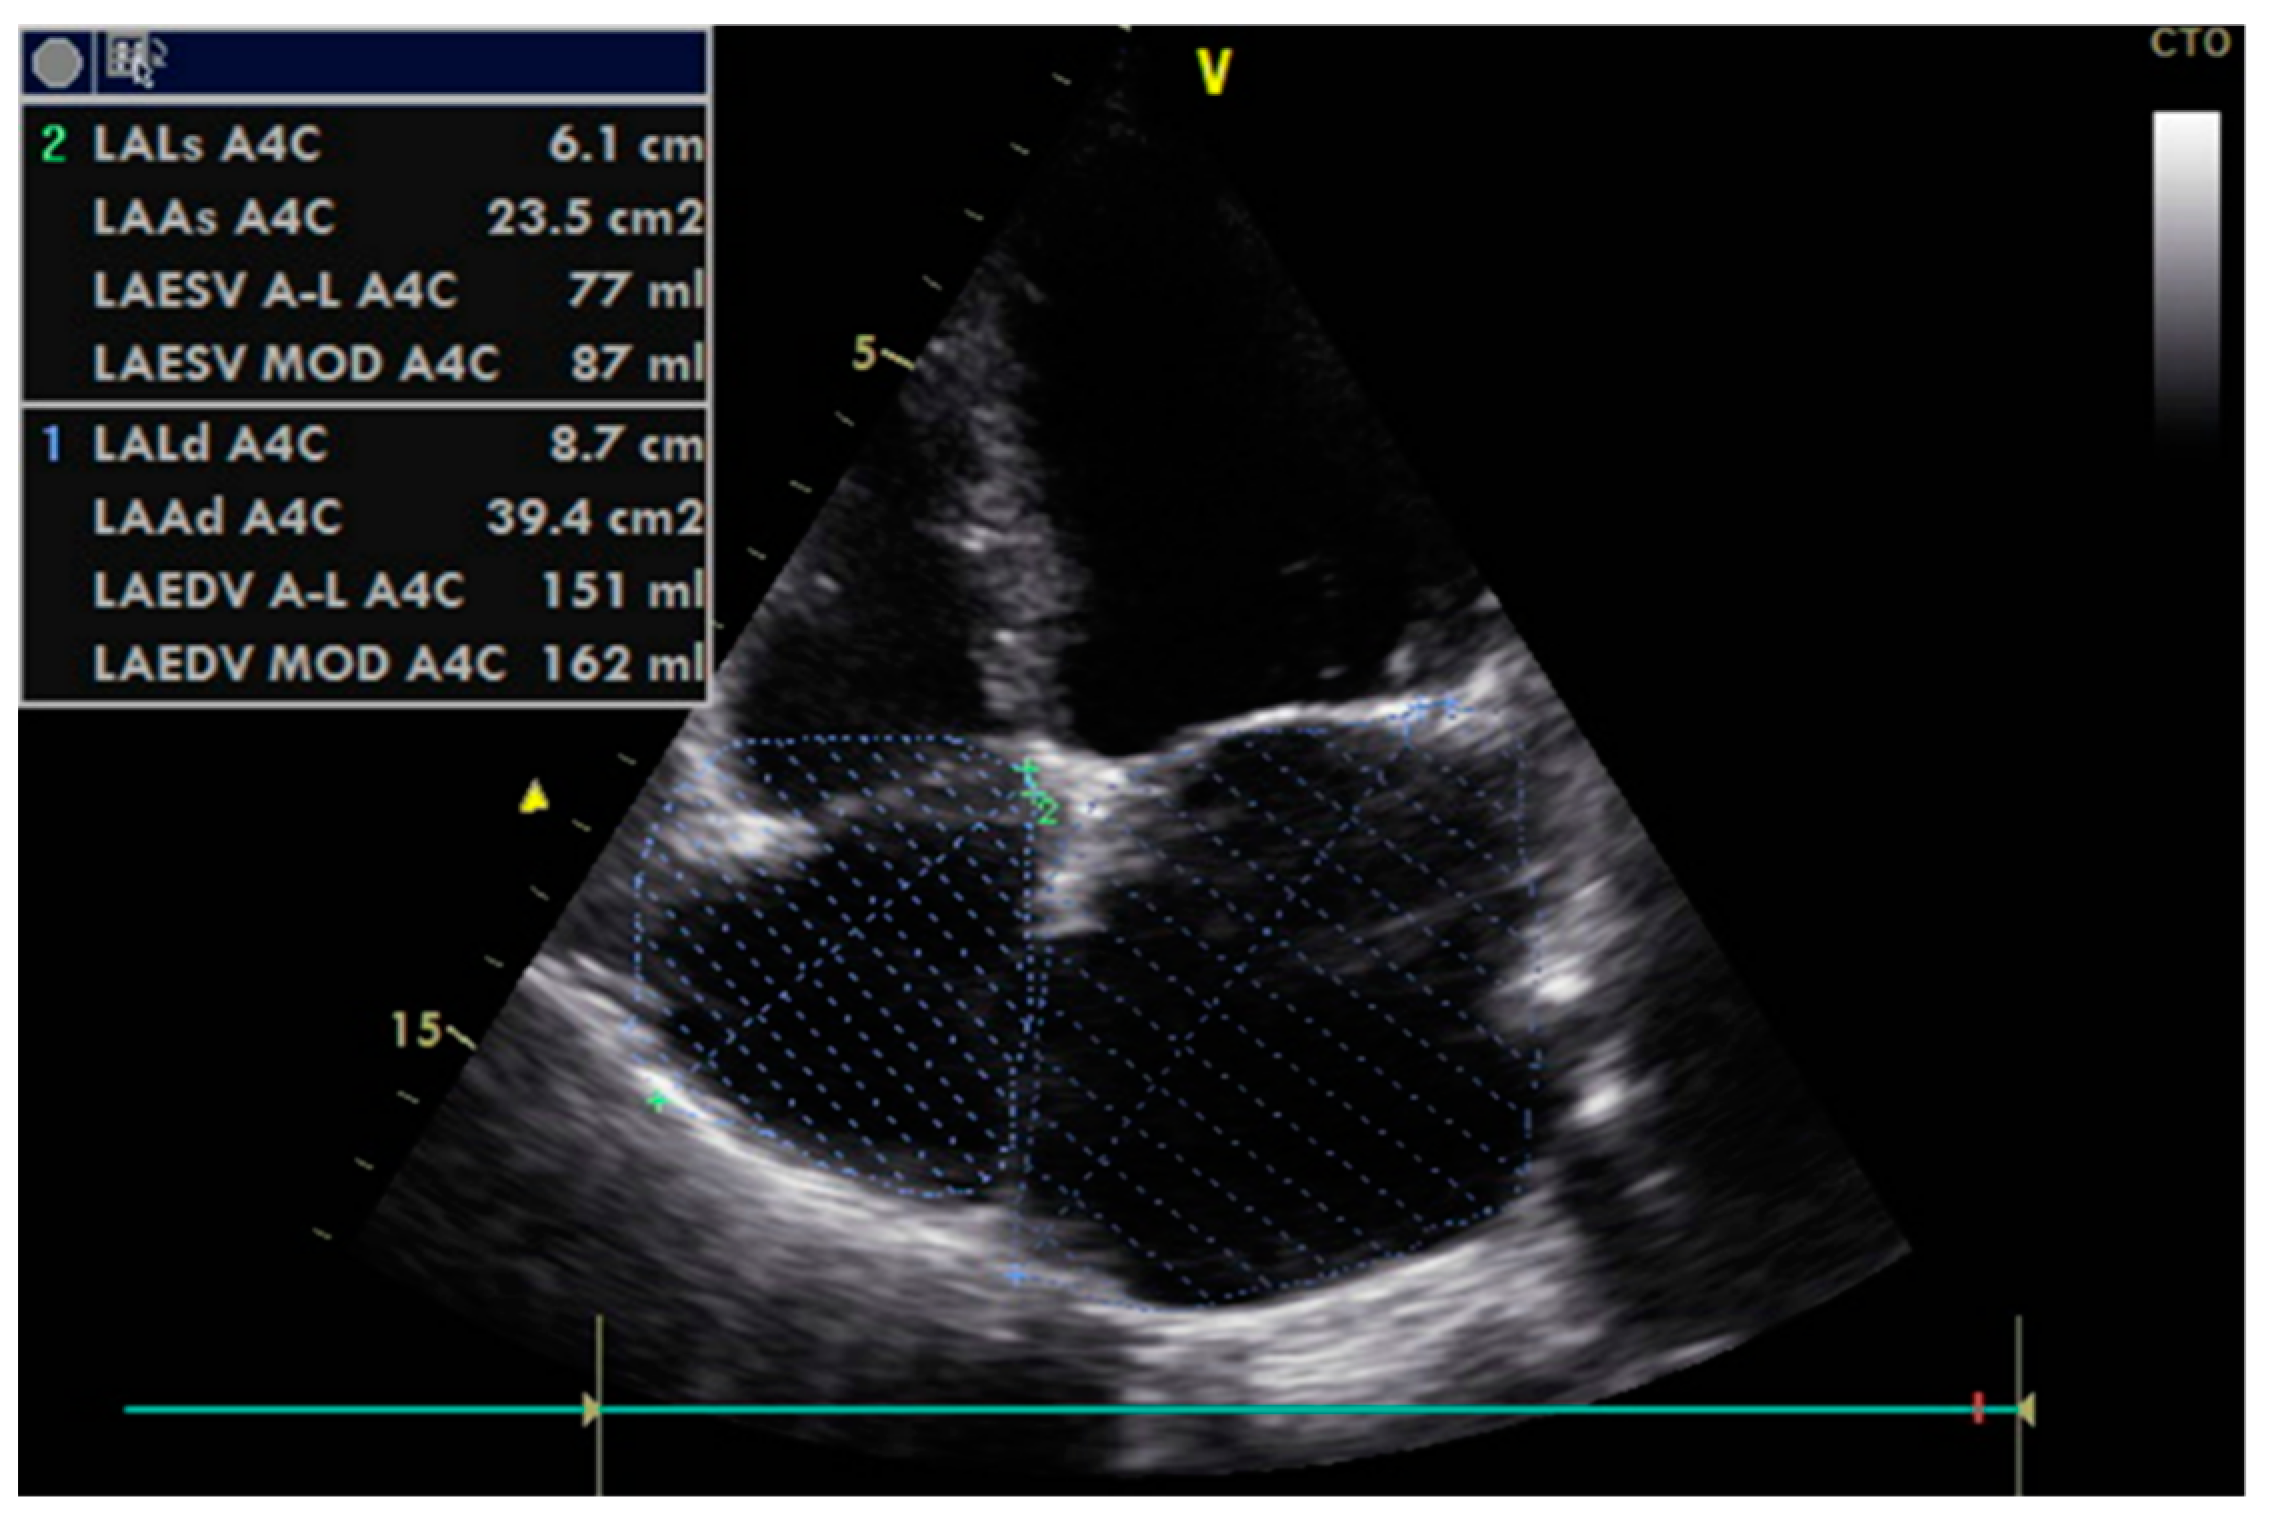

| LAVi (mL/m2) | T0 | 43.40 ± 11.57 | 45.15 ± 12.42 | 0.595 |

| T1 | 43.32 ± 10.55 | 45.49 ± 12.55 | 0.496 | |

| Δ | −0.082 ± 8.80, p = 0.937 | 0.341 ± 8.53, p = 0.799 | 0.804 | |

| LA area (cm2) | T0 | 24.49 ± 4.34 | 24.14 ± 4.34 | 0.605 |

| T1 | 24.15 ± 4.19 | 24.23 ± 4.50 | 0.913 | |

| Δ | −0.34 ± 3.07, p = 0.288 | 0.09 ± 2.55, p = 0.812 | 0.417 | |